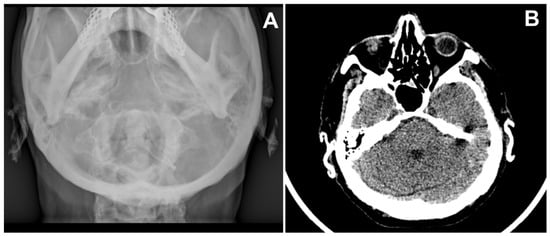

A 71-year-old man was referred for surgery for a squamous cell carcinoma of the left scapha (Figure 1A). He recalled progressive stiffening of both ears for 20 years, associated with pain exacerbated in bed at night, and complained of hearing loss. He denied a history of ear trauma, frostbite, or inflammatory disorders. He had an 18-year history of primary hypothyroidism and primary adrenal insufficiency, currently treated with hydrocortisone and levothyroxine. At palpation, both ears were stony hard, inflexible, and unmalleable (Figure 1B), without any visible external change, apart from the carcinoma. No alterations of the nasal ala were observed. A radiograph (Figure 2A) and a computerized tomography scan (CT) showed calcification of the entire auricular cartilage with sparing of the earlobes (Figure 2B). Full blood cell count, renal biochemistry, calcium, phosphorus, glucose, uric acid, thyroid function, and parathyroid hormone tests revealed normal findings. A diagnosis of petrified ears was made. No specific treatment of the calcification was performed due to the mild symptom entity. The squamous cell carcinoma was surgically excised to the calcified plane, with negative surgical margins (Figure 3). Reconstruction of the surgical defect was accomplished with a two-stage interpolated, inferiorly based, pre-auricular transposition flap (Figure 4). Immediately after the excision, the flap was incised and undermined, and its distal end was transposed and sutured to the ear defect. After 3 weeks, the pedicle of the flap was severed, and remodeling and final suturing were performed. The donor site was primarily closed.

Figure 2. (A) X-ray of the skull showing opacification of both helices; (B) Computerized tomography of skull reveals calcification of right and left pinna.